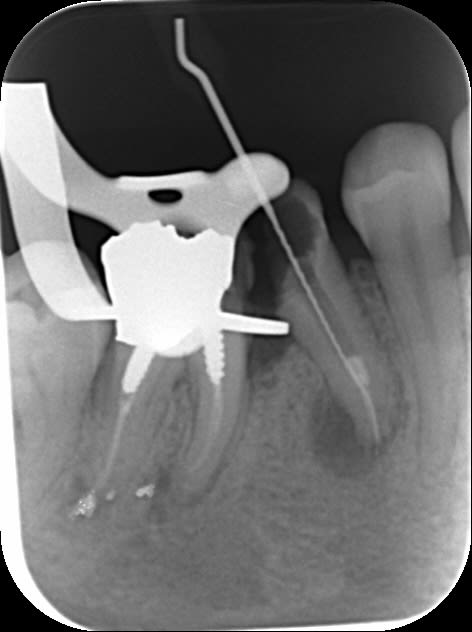

2 retraitements endo sur 45 46.

2 m85na9 - Eugenol

3 j2ewih - Eugenol

4 mbyxz8 - Eugenol

1 ojgvk3 - Eugenol